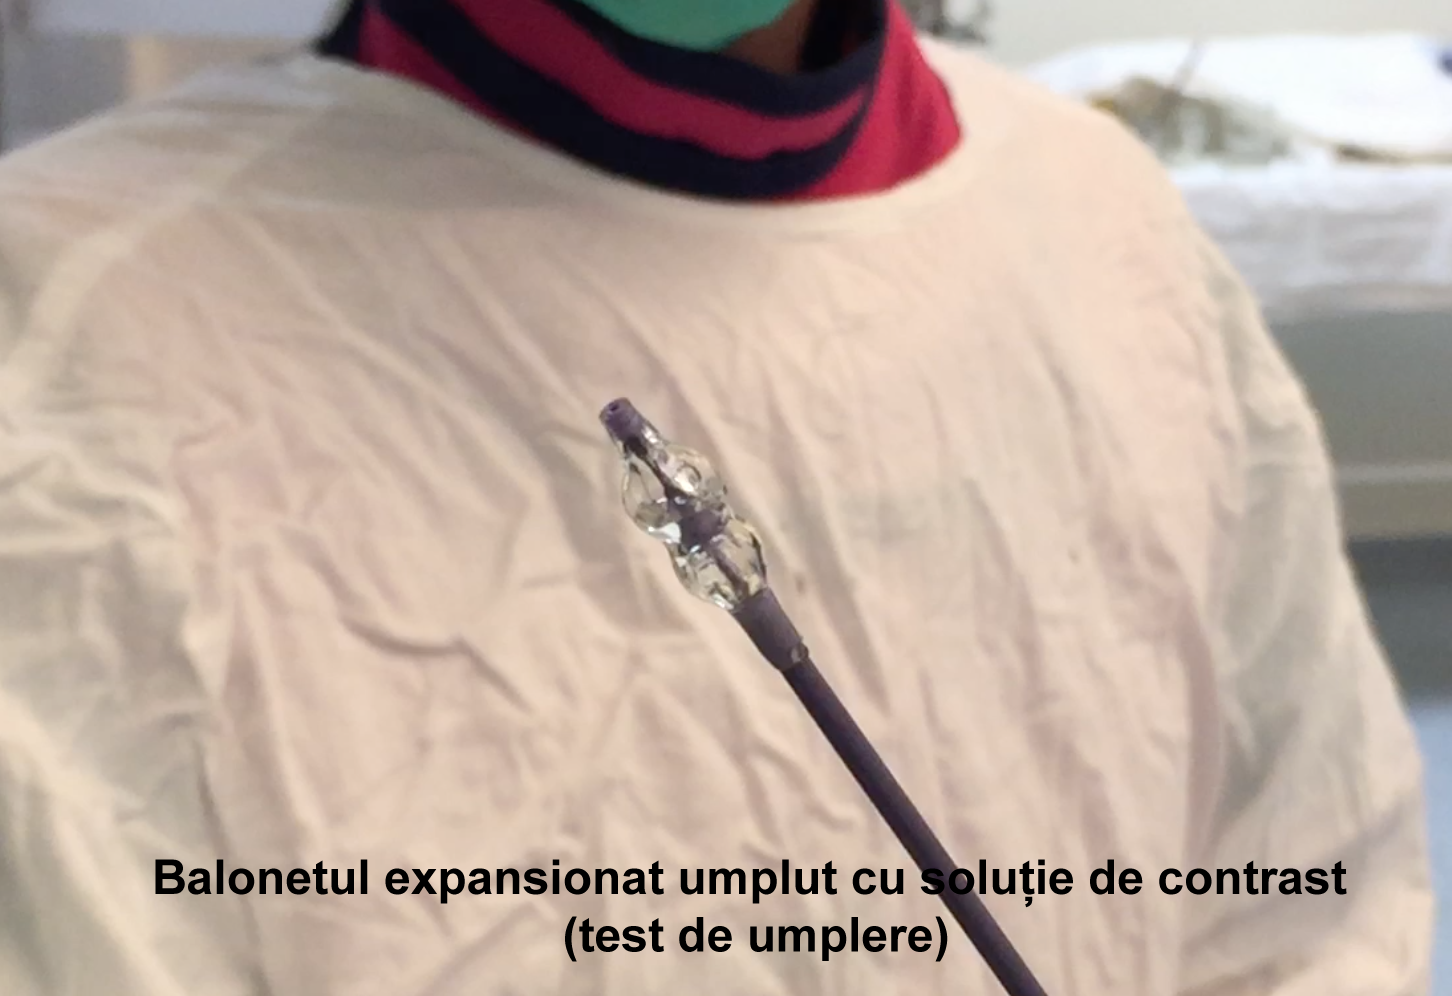

Kyfoplastia reprezintă o procedură minim invazivă în timpul căreia chirurgul introduce în corpul vertebral un tub cu un balon expandabil. Sub control fluoroscopic are loc expansionarea balonului în corpul vertebral, cu restabilirea înălţimii corpului vertebral şi corijarea diformităţii kifotice. Ulterior, în cavitatea formată de balon, se introduce cimentul acrilic, ceea ce contribuie la consolidarea vertebrei.